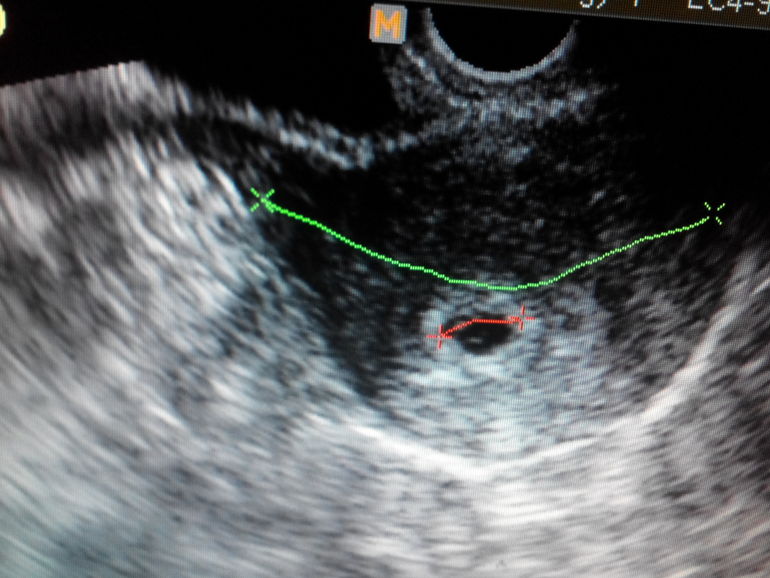

А вот и наш второй малыш (под красной линией маленькая серая полосочка). УЗИ во вторник, 25.08 делала. Завтра ещё одно - будут смотреть, развивается ли моя крошечка. Должно забиться сердечко!!! Узистка, правда, велела повторить через неделю (мне тоже кажется, что завтра рано).